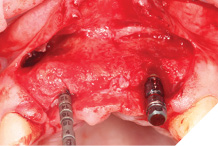

Straumann Bone Level tapered implants were placed as per the planning above and following the Straumann drill placement protocol. We collected the autogenous bone chips from the flutes of the drills as part of the osteotomy site preparation.

Full Depth Direction Indicators were used to check correct implant angulations for screw retained restorations. The implants were almost wholly within autogenous alveolar bone – however we clearly needed to reinforce and thicken the buccal profile for long-term implant health and gingival stability (Figs. 13-18).

Fig. 13

Fig. 14